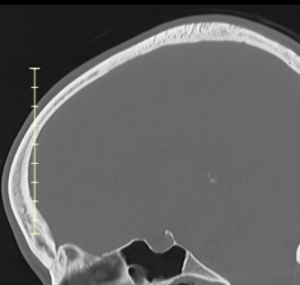

Aesthetic improvement of frontal bossing is achieved through bony reduction using burring or shaving of the frontal bone. In cases with fronto-temporal bossing, the bone reduction extends laterally toward the temporal bone, requiring contouring of the bony temporal line and sometimes partial removal or repositioning of the temporal muscle. The extent of achievable reduction depends on the thickness of the frontal bone, which must be evaluated preoperatively using a 3D CT scan.

This young female patient presented with congenital frontal bossing and a broad head shape. Childhood photographs confirmed that the condition had been present since infancy. Her primary concern was the size and convexity of her forehead, though she was not bothered by her relatively high hairline.

Frontal bossing with lateral head widening is congenitally determined and likely influenced by early brain growth patterns. It is not typically caused by excessive bone thickness; in fact, the bone may be thinner than average. Consequently, complete normalization of the forehead contour is rarely achievable, as the degree of reduction is limited by bone thickness—particularly over the upper forehead and along the temporal lines.